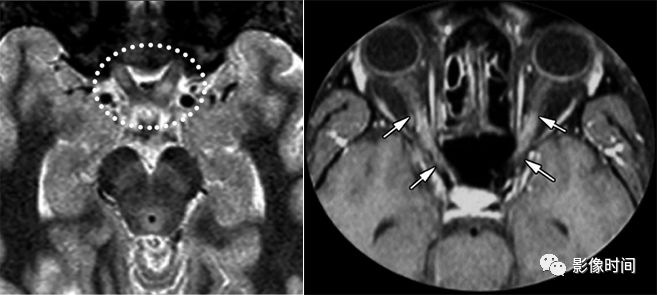

神经脊髓炎谱系疾病(neuromyelitis optica spectrum disorder,NMOSD):是一种由水通道蛋白-4(AQP-4)自身抗体介导的炎性脱髓鞘疾病,青年或中年女性较多见,临床常为双侧视神经炎和脊髓炎导致失明和截瘫,也可累及大脑。

MRI:

脊髓:病灶 T2WI 呈高信号,T1WI 呈稍低信号,急性期出现斑片状或云雾状强化,轴位常位于脊髓中央,长度>3 个椎体长度。亮点征:轴位 T2WI 很高信号的多发斑点,信号高于脑脊液,特异性=97%。

病灶分布于脊髓中央,长度大于3个椎体,亮点征

视神经:双侧视神经广泛受累,病灶长度通常>1/2 视神经长度,优先损害后视通路,包括视神经颅内段、视交叉和视束,急性期 T2WI 视神经肿胀伴明显高信号,T1WI 视神经明显强化,后视通路为主。

后视路受累为主,明显强化

大脑:AQP4 通道是中枢神经系统最丰富的水通道,在室管膜周围、下丘脑和软脑膜下区以及脑干、极后区均有高表达。因此,高表达 AQP4 的特定区域成为 NMO 自身免疫靶点